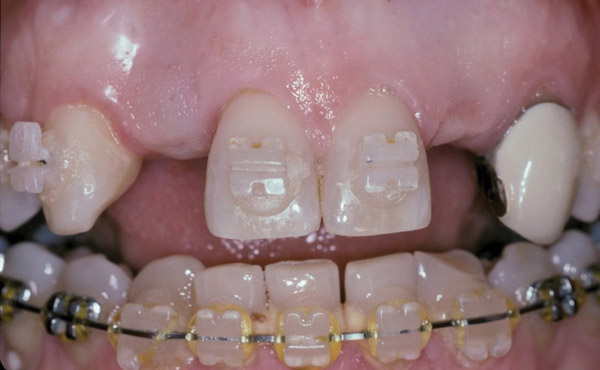

Figure 7  Completion of maxillary orthodontic treatment created adequate space for implants at site Nos. 7 and 10. The retained right primary maxillary canine was extracted and orthodontic movement was performed to translate the right permanent canine into the No. 6 position, creating room for a No. 7 implant, and generally align the teeth.

Figure 7